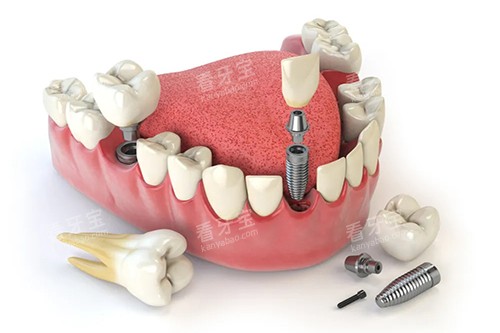

例如,在牙齿正畸方面,医生会根据患者的牙齿情况、面部特征和个人需求,制定出较适合的正畸方案;在种植牙领域,医生能够熟练运用各种靠前的种植技术,为患者解决牙齿缺失的问题。

为了给患者提供更加比较准、较高的效率的口腔医疗服务,大连齿医生口腔引进了一系列国内外靠前的口腔医疗设备。

这些设备包括智能化口腔全景机、口腔 CT、激光治疗仪等。

在种植牙方面,大连齿医生口腔的种植成功几率非常高,患者在种植牙齿后,能够修养正常的咀嚼功能,提高生活质量。